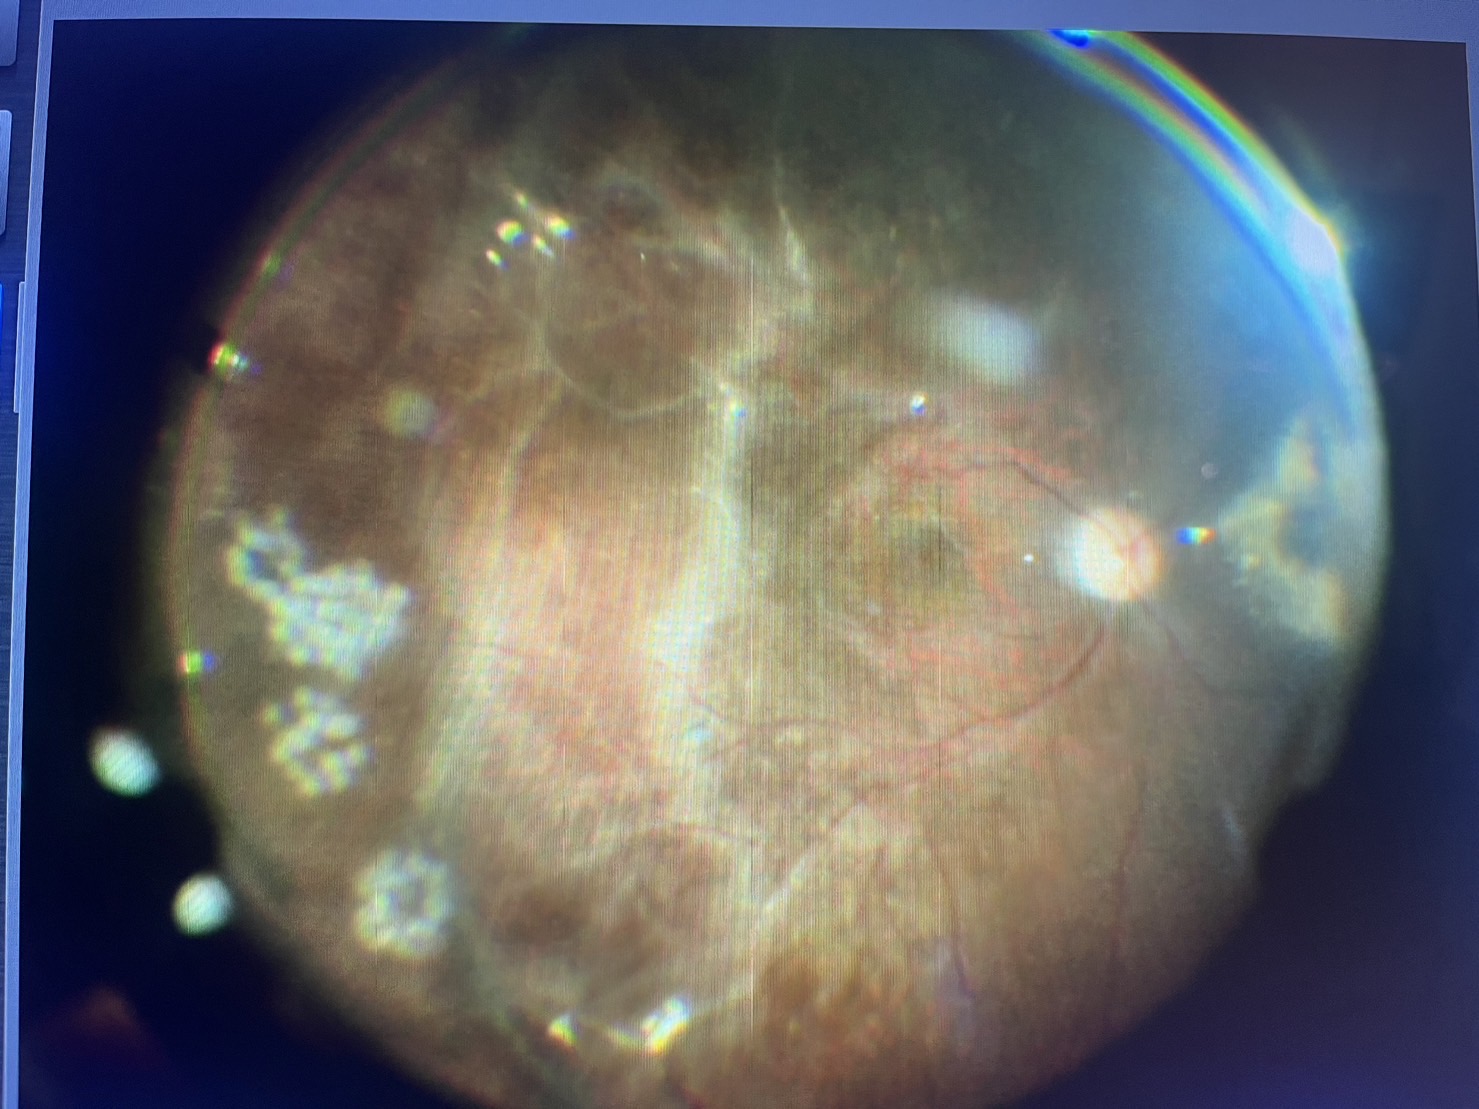

白内障が強い場合の硝子体手術の懸念点は眼底の様子が事前に分からないことで、今回もOCTという検査で黄斑の上の膜が分かっていたものの、実際に眼の中を見る眼底検査はできない程の白内障の濁りで、白内障を取って、硝子体の中に入ると、単なる年齢の黄斑上膜ではなく、おそらく、静脈閉塞症という眼底出血を起こす病気を起こし、それによって続発的に生じた黄斑上膜のような所見でした。硝子体手術では、硝子体の外側の膜を網膜から剥がしていくのですが、部分的にくっつきが強く、丁寧に剥がしたものの、2〜3か所、網膜に小さな穴があいてしまったため、レーザーで穴の周りを固め、念のため、眼の中をガスに換えて手術を終えました。予想外の眼底所見で、思ったより時間がかかってしまいましたが、白内障が強かったり、硝子体出血などで眼底が分からない場合の手術は、色々な可能性があり、開けてびっくりとならないように、しっかり術前の説明をし手術に備えようと改めて思いました。